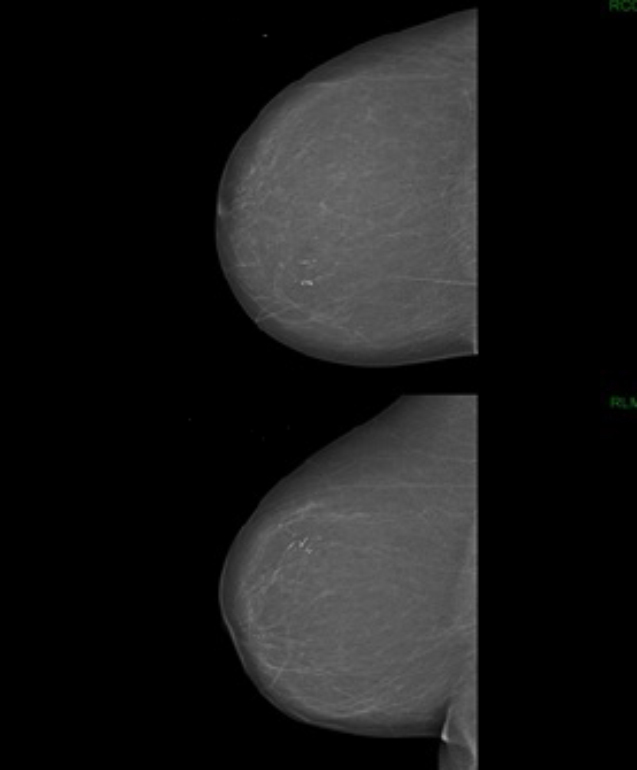

La mammographie montre l’aspect suivant :

Question 4 - Vous tirez les conclusions suivantes :

Il s’agit du quadrant supéro-interne, ce qui correspondait par ailleurs plus à la clinique.

On voit une anomalie (microcalcification) et la mammographie est donc à classer au moins ACR2. Par ailleurs, cette mammographie serait probablement classée ACR5.

Il faut réaliser une micro-biopsie (ou macro-biopsie si la lésion est difficilement palpable)

Pour rappel, concernant la classification de l’American College of Radiology (ACR) sur l’aspect d’une mammographie :

– ACR1 : mammographie normale ; – ACR2 : anomalie bénigne (pas de surveillance ni d’examen complémentaire) ; – ACR3 : anomalie probablement bénigne à surveiller : surveillance à court terme (mammographie à 3-6 mois) ou biopsie ; – ACR4 : anomalie suspecte nécessitant une histologie → microbiopsie ou macrobiopsie selon la situation ; – ACR5 : lésion d’allure maligne → microbiopsie ou macrobiopsie.

Par ailleurs, pour la lecture d’une mammographie, il faut retenir les repères suivants :

– sur le cliché de face : quel que soit le sein, la partie supérieure du sein représente le quadrant externe, et la partie inférieure représente le quadrant interne ; – sur le cliché oblique externe : au-dessus du mamelon = quadrants supérieurs, en-dessous = quadrants inférieurs.

Ci-joint un cliché pour vous aider à comprendre cette mammographie :